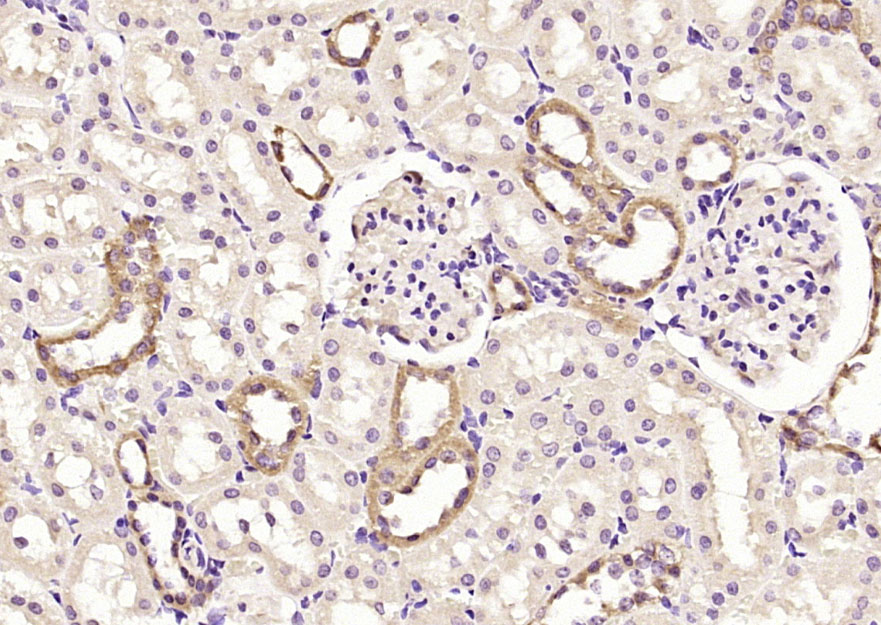

| 英文名称 | GALK2 Rabbit pAb |

| 中文名称 | 半乳糖激酶2抗体 |

| 产品应用 | IHC-P=1:100-500, IHC-F=1:100-500, IF=1:100-500 Not yet tested in other applications. |

| 背景资料 | GALK2 is important in the first step of the galactose metabolism pathway. GALK1, which belongs to the GHMP kinase family of proteins, is a crucial enzyme for galactose metabolism, specifically converting ?d-galactose to galactose 1-phosphate. Defects in the gene encoding GALK1 can cause galactosemia II, an autosomal recessive disorder characterized by congenital cataracts during infancy, often within the first two weeks of life. In the adult population, galactosemia II can cause presenile cataracts that are secondary to accumulation of galactitol in the lens of the eye. A second gene, GALK2, encodes an enzyme with greater activity against GalNAc than galactose. GALK2 has been implicated in the salvage pathway for the reutilization of free GalNAc derived from the degradation of complex carbohydrates. |

| {IHC-P} | {1:100-500} |